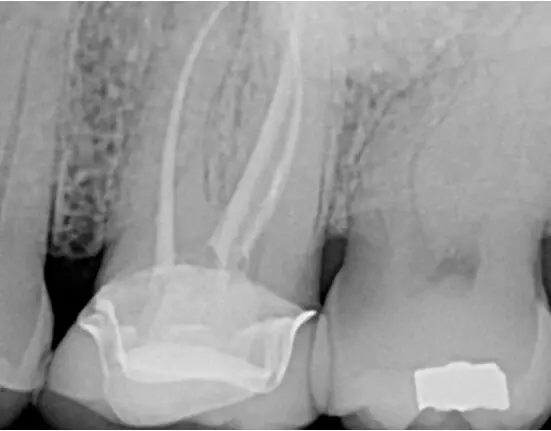

Another dentist referred a patient to me. While the dentist did a great job on the patient’s root canal, the patient was still experiencing pain. The 2-D image did not show significant pathology, and the root canal fill looked good (Figure 1).

I performed a large field of view 3-D CBCT to get more information about the case (Figure 2). It revealed a periapical pathology associated with the mesiobuccal root, which usually means there is a missed second mesiobuccal canal (MB2).